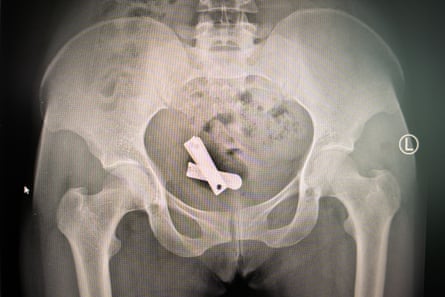

In June, the Guardian revealed a pattern of extreme sexual violence where soldiers forced foreign objects – including metal screws, stones and other debris – into women’s reproductive organs. In at least two cases, the soldiers inserted plastic-wrapped letters detailing their intent to destroy Tigrayan women’s ability to give birth.